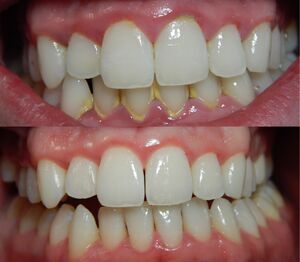

حالة التهاب لثة حادة. | |

التهاب اللثة (إنگليزية: Gingivitis)، هو هو مرض غير مدمر يسبب التهاب في اللثة.[1] الشكل الأكثر شيوعًا من التهاب اللثة، والشكل الأكثر شيوعاً من أمراض دواعم الأسنان بشكل عام، هو الاستجابة لبكتريا الأغشية الحيوية (وتسمى أيضًا اللوحة السنية أو البلاك) التي تعلق على أسطح الأسنان، يطلق عليه "التهاب اللثة الناجم عن البلاك". تحدث معظم أشكال التهاب اللثة بسبب البلاك.[2]